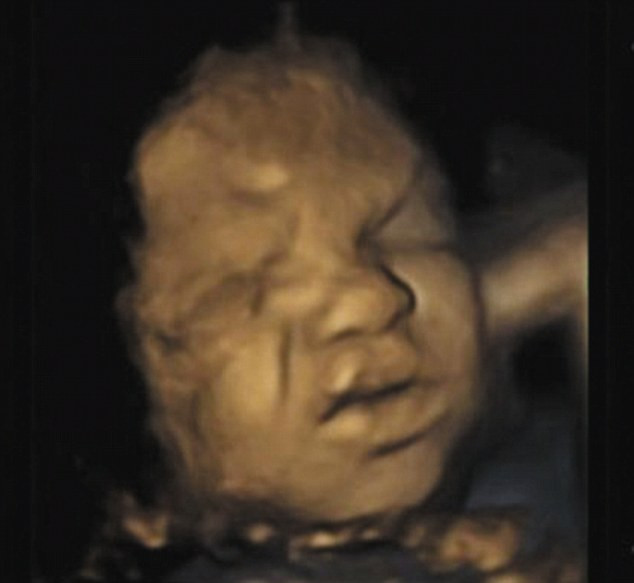

In ecografii sunt surprinse in cele mai mici detalii gesturile fetei pe care copiii din pantece le fac.

Imaginile au fost realizate cu ajutorul unui ecograf 4D care reuseste sa surprinda copilul in pantece in cel mai marunt detaliu posibil.